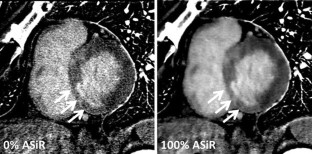

Single-source dual-energy CT (ssDECT) allows the reconstruction of iodine density images (IDIs) from projection based computing. We hypothesized that adding adaptive statistical iterative reconstruction (ASiR) could improve image quality. The aim of our study was to evaluate the effect and determine the optimal blend percentages of ASiR for IDI of myocardial late iodine enhancement (LIE) in the evaluation of chronic myocardial infarction using ssDECT. A total of 28 patients underwent cardiac LIE using a ssDECT scanner. IDIs between 0 and 100% of ASiR contributions in 10% increments were reconstructed. The signal-to-noise ratio (SNR) of remote myocardia and the contrast-to-noise ratio (CNR) of infarcted myocardia were measured. Transmural extent of infarction was graded using a 5-point scale. The SNR, CNR, and transmural extent were assessed for each ASiR contribution ratio. The transmural extents were compared with MRI as a reference standard. Compared to 0% ASiR, the use of 20–100% ASiR resulted in a reduction of image noise (p < 0.01) without significant differences in the signal. Compared with 0% ASiR images, reconstruction with 100% ASiR image showed the highest improvement in SNR (229%; p < 0.001) and CNR (199%; p < 0.001). ASiR above 80% showed the highest ratio (73.7%) of accurate transmural extent classification. In conclusion, ASiR intensity of 80–100% in IDIs can improve image quality without changes in signal and maximizes the accuracy of transmural extent in infarcted myocardium.

Fig. 1